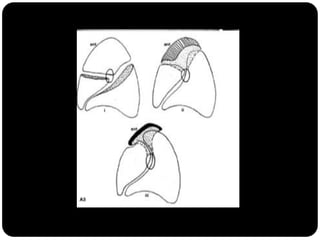

Atelectasia

 Diminuição de volume do segmento, deslocamento de uma ou mais

fissuras interlobares em direção à parte atelectasiada, desvio do mediastino

para o lado envolvido, deslocamento hilar, estreitamento dos espaços

intercostais e hiperinsuflação dos outros lobos / segmentos não atelectasiados

Ex: Colapso do

LSD

Observar

deslocamento de

fissura!

Atelectasia do lobo

superior direito